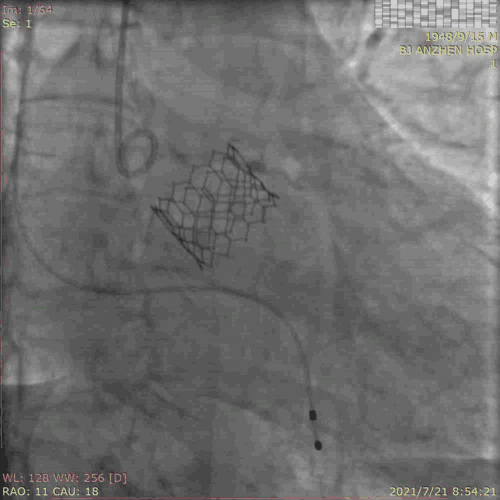

TAVR过程:患者局麻后,植入临时起搏器,穿右股动脉送入23mm球囊预扩张病变,左、右冠状动脉未受明显影响,决定直接植入爱德华SAPIEN 3 26mm 球扩式瓣膜,选择标准位进行释放。

释放后主动脉窦造影提示瓣膜膨胀良好,主动脉瓣周少量反流。术后即刻TTE提示跨瓣最高流速109cm/s,平均跨瓣压差3mmHg。主动脉瓣瓣口面积2.72cm²。